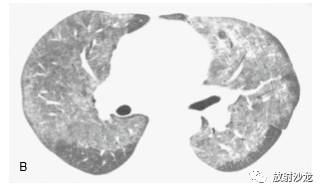

因为磨玻璃影反映存在纤维化或炎症,诊断 时要小心,仅在不伴有HRCT 纤维化表现,或以 磨玻璃影为主要表现时诊断(图 5-5 ~图 5-8)。如磨玻璃影仅见于有牵引性支气管扩张或蜂窝等 HRCT 的纤维化改变的肺区内,纤维化可能将使 主要的组织学异常(图5-4,图5-9)。例如,在 Remy-Jardin 等的一项研究中,所有 HRCT 上的磨 玻璃影区内有牵引性支气管扩张或细支气管扩张 的病例,活检都有纤维化。然而,在不伴有牵引 性支气管扩张的磨玻璃影区的病例中,肺活检时 92% 发现有活动性炎症。

在有磨玻璃影的病例中,组织学异常的类型 根据疾病的典型组织学表现而异,无特异性组织学改变(表 5-2)。在 NSIP、硬皮病或 其他胶原血管病病例中,许多研究曾结合CT 上 的磨玻璃影和活检结果、治疗反应和病例的生存期。在间质性肺炎病例的组织学研 究中曾显示,大部分磨玻璃影和肺泡壁或肺泡内炎症相关。例如,在一项Wells 等的硬皮病研究中,HRCT 上的致密度增加和7 例活检中4例的明显炎症相关,而在HRCT 上的网影中,13 例中12 例为纤维化。另一项14 例HRCT 表现为 磨玻璃影的特发性肺纤维化(IPF)病例中,活检 12 例有炎症。在寻常性间质性肺炎(UIP)病 例中,磨玻璃影伴有不等的肺纤维化;有磨玻璃 影的DIP 病例在很大程度上反映肺泡内有巨噬细胞。